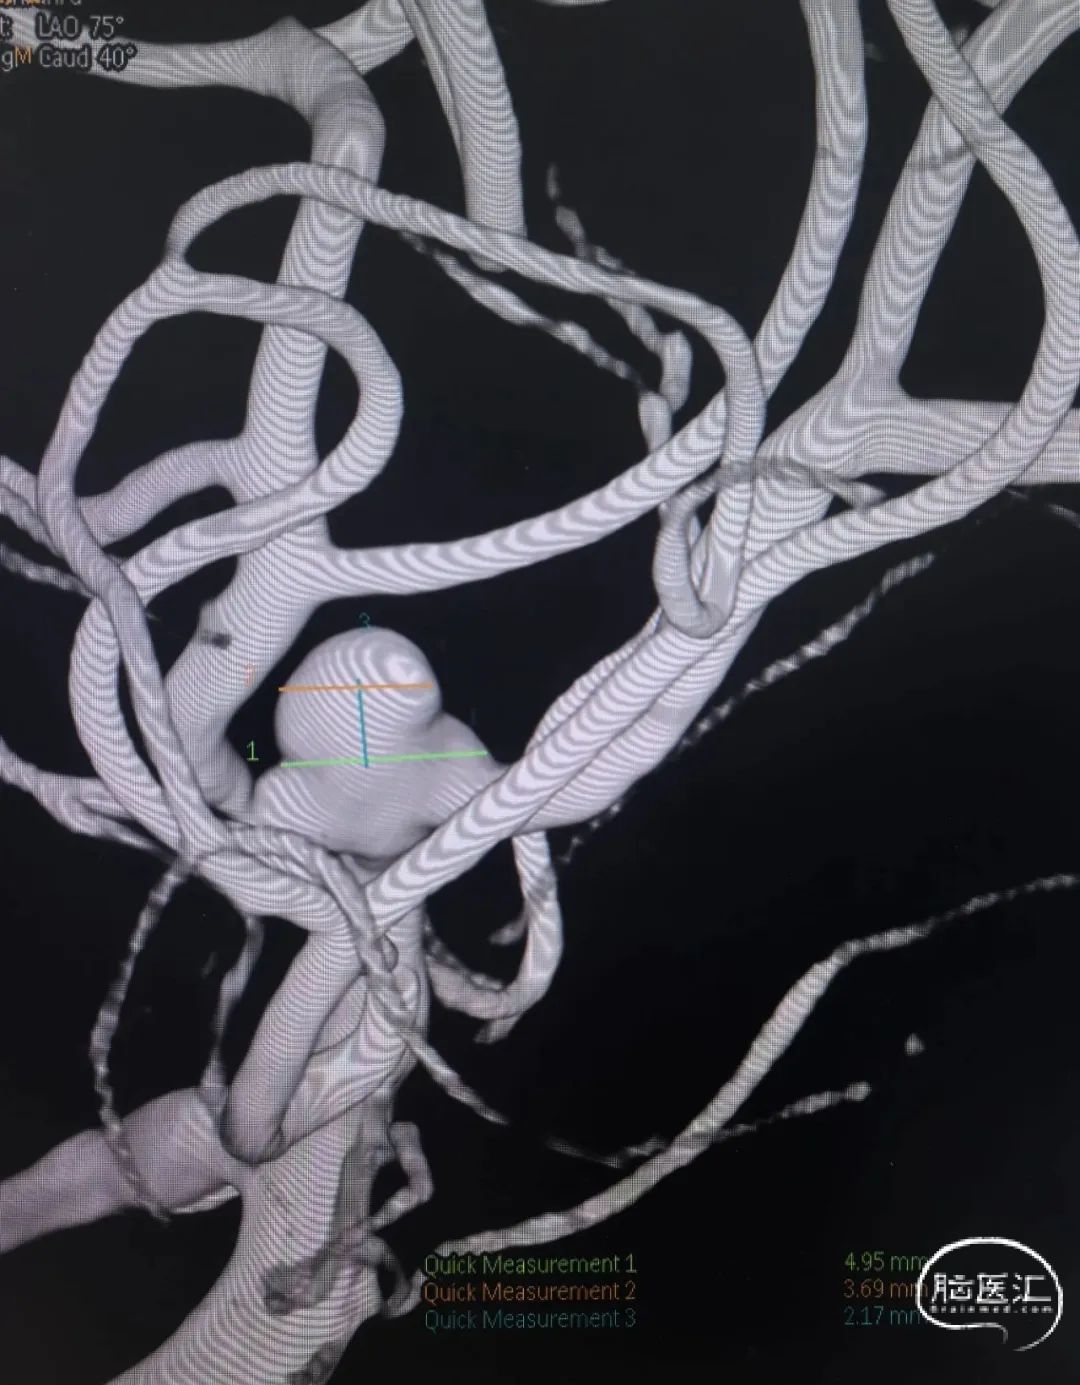

多角度测量评估:动脉瘤平均瘤宽4.0mm,平均瘤高3.1mm,平均瘤颈宽3.66mm。

动脉瘤测量

经多角度测量,动脉瘤平均瘤宽3.56mm,平均瘤高2.17mm,平均瘤颈宽4.63mm。